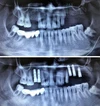

علاج الزرع السني

التهاب ما حول الزرعة السنية (Periimplantitis)

التهاب الغشاء المخاطي حول الزرعة السنية (Peri-İmplant Mukozitis)